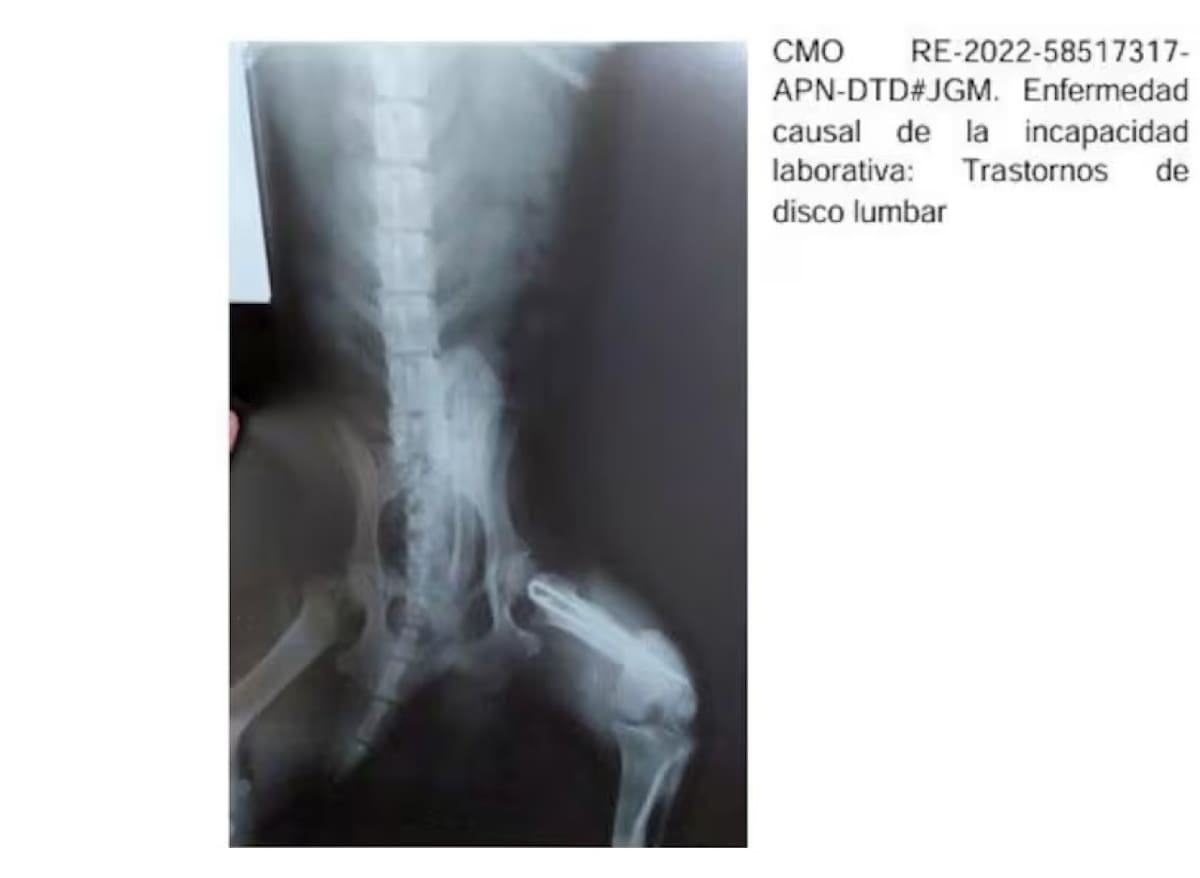

También hizo público el caso de la provincia de Chaco, donde una misma radiografía de hombro fue presentada como prueba en 150 pensiones por invalidez. Mientras que en 2022 “un médico correntino de dudosa ética profesional adjuntó al certificado que presentó para la obtención de una pensión la radiografía de un perro”, material cuya copia el Vocero compartió entre los periodistas presentes en la conferencia ya que en la imagen se puede ver la cola del perro.

Radiografía de un perro usada para obtener una pensión por discapacidad. Foto: Prensa

"Para obtener una pensión por un trastorno de disco lumbar e hipertensión, un médico correntino de dudosa ética profesional adjunto junto al certificado la radiografía de un perro con una particularidad. ¡Tiene la cola del perrito! Y le otorgaron la pensión", expresó dijo Adorni durante la conferencia de este viernes.

"Lo que suena increíble, porque uno puede confundir cualquier cosa ¿no?, es la cola del perrito... Qué se pensaban que era... Qué era la cola, bue... Este era el nivel de descontrol que había en las pensiones por discapacidad", agregó el vocero.